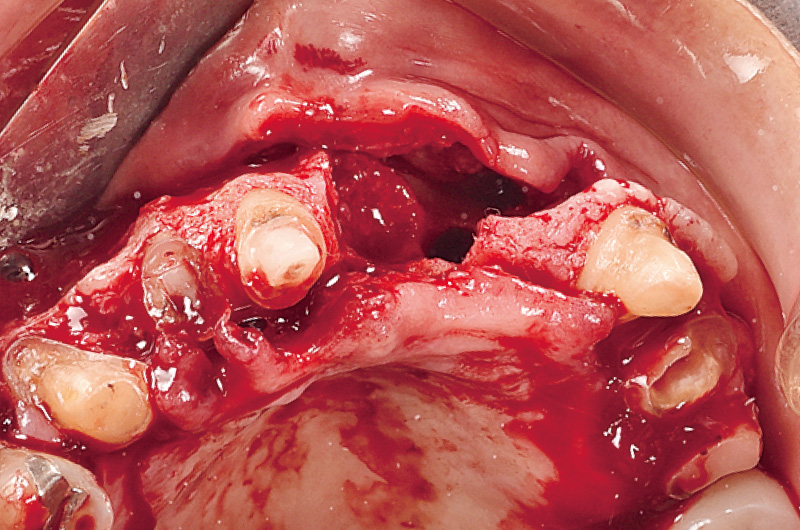

エンドペリオ病変を併発しており、抜歯適応と判断した。11, 12は、太くて長いダウエルコアが装着されていた。12の根尖部に13の埋伏歯を認め、それにより12の歯根が吸収している。保存の可否を判断するために、ロングスパンブリッジを撤去しようとしたこところ、容易に撤去でき、21に関しては歯根ごと抜去された。11, 12は残存歯質が乏しく歯肉縁下だったため、保存不可と判断した。患者の強い希望もあり、インプラントによる補綴設計を計画した(図2)。

図2 11は残存歯質が少なく、唇側は縁下に及んでおり、再介入を考慮し抜歯とした。